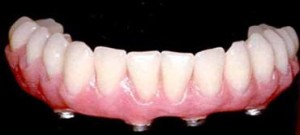

Prosthetic flexibility

With All-on-4, patients benefit from an immediate implant-supported restoration, as a provisional prosthesis is screwed onto the implants right after surgery. Final solutions for All-on-4 include both fixed prostheses, such as NobelProcera Implant Bridge Titanium with acrylic veneering, or individual NobelProcera crowns cemented to the bridge framework, and removable solutions, such as acrylic overdentures on a NobelProcera Implant Bar Overdenture.